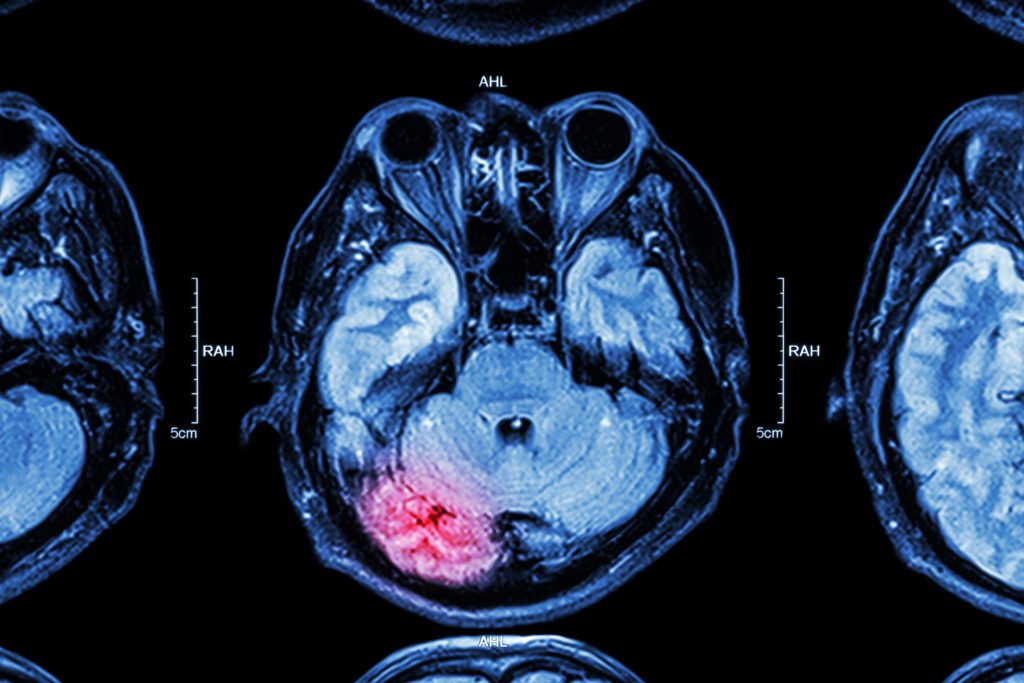

Traumatic brain injury (TBI) is defined as an assault to the brain from an external force that leads to temporary or permanent impairment of cognitive, physical, or psychosocial function. TBI can be open (penetrating) or closed (non-penetrating) and can be categorized as mild, moderate, or severe, depending on the resulting symptomatology. TBI diagnosis is best documented at the time of the injury or within the first 24 hours. During the diagnostic process, a clinician typically assesses the severity of TBI; however, this initial diagnosis does not necessarily predict the extent of disability arising from TBI. The diagnostic process includes neuroimaging, assessing the presence of an altered consciousness or loss of consciousness, assessing the presence of posttraumatic amnesia, and applying the Glasgow Coma Scale score. The Department of Defense (DoD) classifies the severity of TBI using a combination of the four factors mentioned above.